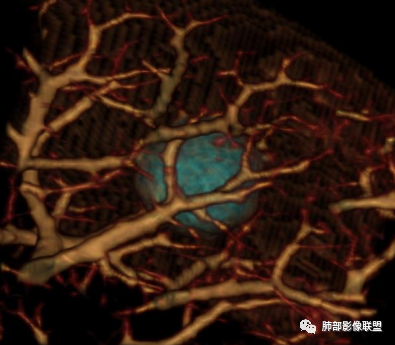

此病例中结节,与支气管无关系,边缘清晰,形态规则,缺乏张力,未见典型的分叶及毛刺,病灶周围磨玻璃为部分容积效应所致,肺门纵隔未见肿大淋巴结,良性病变可能性较大,肺部的良性肿瘤中,最常见的是错构瘤,其次是硬化性肺细胞瘤(PSP),第三是孤立性纤维性肿瘤(SFT)。

肺错构瘤

常表面光滑,可有浅分叶或无分叶,无毛刺,对周围肺组织无牵拉;常挂枝头(挂在肺动脉枝头上),很少到达胸膜。出现脂肪成分,或者典型的爆米花样钙化几乎可以确诊,软骨型错构瘤因软骨组织多,强化弱。平滑肌型错构瘤增强有一定强化。病灶周围边界清楚,常有很低密度的黑晕。

综上所述,错构瘤可能性最大